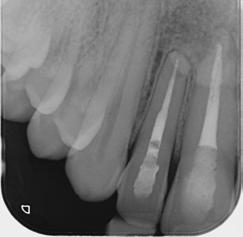

This is not a “Terminal Dentition”. It is interesting to see the increase in patients being advised that Periodontitis is not treatable or that treatment is somehow expensive and ongoing maintenance is difficult/unachievable. These patients are usually advised to receive implant treatment as an alternative.

This patient first presented in 2016 at the age of 33 years. He was a former smoker (quit two years prior to the initial presentation). He presented with generalised deep pocketing and advanced loss of attachment.

2023 show stable bone levels with no evidence of further bone loss.

Radiographic assessment showed generalised moderate to advanced bone loss with most teeth showing bone loss to more than 50% of the root length. Given the established loss of attachment in relation to his relatively young age, this patient was diagnosed with generalised aggressive periodontitis. According to the 2017 Classification of Periodontal Disease, he would be Stage III, Grade C Periodontitis.

The patient was managed with non-surgical periodontal debridement. Two months later, he presented with an encouraging reduction in periodontal probing depth (PPD). There were 85% sites with PPD 1-3mm, 15% sites with PPD 4-5mm and no sites with residual PPD > 6mm. The patient showed excellent plaque control measures and his bleeding on probing score was 1%. The patient has been placed on a six-monthly periodontal maintenance program with the periodontist. He also sees his general dentist once annually. The OPG images dated 2016 and

The patient had orthodontic treatment between 2018-2020 to address the flaring and spacing of his teeth, which was a cosmetic concern to him (orthodontic treatment done by Dr Frank Furfaro). Long-term evidence shows that we, as dental clinicians, are not accurate at determining the prognosis of periodontally compromised teeth (McGuire 1996). We may also be hasty at labelling such teeth as “hopeless”. The threshold at which we

decide to extract teeth due to periodontal disease may be too low (Splieth 2002). There is no evidence on the other hand that dental implants have longer survival or less complications or better cost compared to periodontally treated teeth.